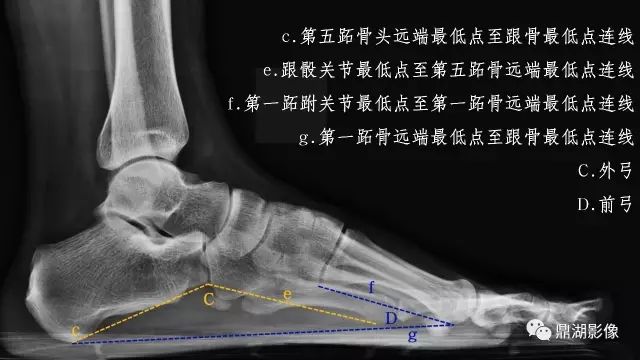

影像检查

辅助检查方法主要是X线检查,应负重条件下摄足正侧位X线片,主要在足侧位片测量足弓的角度改变。